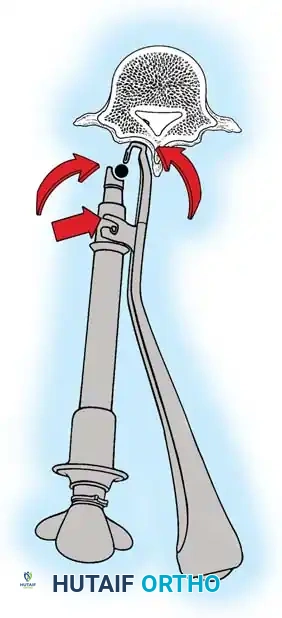

The Moe Technique (Lumbar Spine)

In the lumbar spine, the facet joints are oriented in a more sagittal plane, necessitating a modified approach.

Fig. 38-27: The Moe technique adapted for lumbar facet fusion, addressing the sagittal orientation of the joints.

- Utilize a small osteotome or a needle-nose rongeur to resect the adjoining joint surfaces.

- This creates a distinct rectangular defect within the sagittally oriented joint space.

- Pack this defect forcefully with cancellous bone graft.

- Proceed to decorticate the entire exposed posterior elements (laminae and transverse processes) using Cobb gouges, always directing force away from the spinal canal.